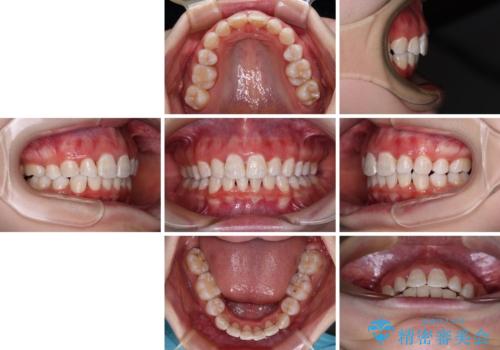

叢生・ディープバイト・突出 ワイヤー装置での抜歯矯正で全てを解決

ディープバイトは、治療を行っていた我々も驚くほど、短期間で劇的に改善することができました。

骨格的に下顎骨が左側にシフトしていたため、上下正中の位置や左側臼歯部の咬合を理想的に仕上げることはできませんでしたが、非常に綺麗な口元を達成することができました。